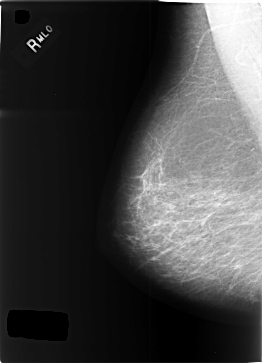

Digital Database for Screening Mammography

Volume: cancer_09 Case: C-0345-1

C_0345_1.LEFT_MLO

DATE_OF_STUDY 28 11 1997

PATIENT_AGE 59

DENSITY 2

LEFT_MLO LINES 5816 PIXELS_PER_LINE 4216 BITS_PER_PIXEL 12 RESOLUTION 50 OVERLAY

FILE: C_0345_1.LEFT_MLO.OVERLAY

TOTAL_ABNORMALITIES 2

ABNORMALITY 1

LESION_TYPE CALCIFICATION TYPE PLEOMORPHIC DISTRIBUTION SEGMENTAL

ASSESSMENT 5

SUBTLETY 5

PATHOLOGY MALIGNANT

ABNORMALITY 2

LESION_TYPE MASS SHAPE LOBULATED MARGINS CIRCUMSCRIBED